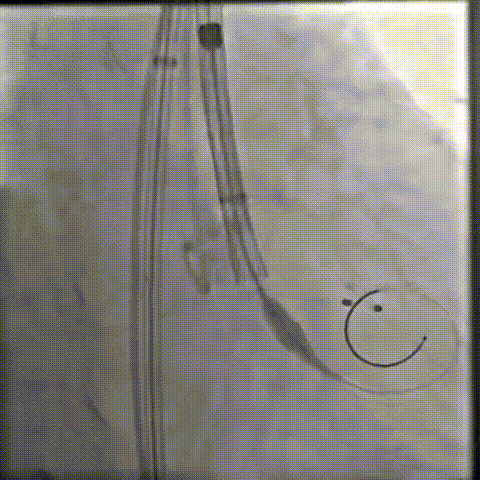

器械过弓柔顺

初始定位

释放瓣膜